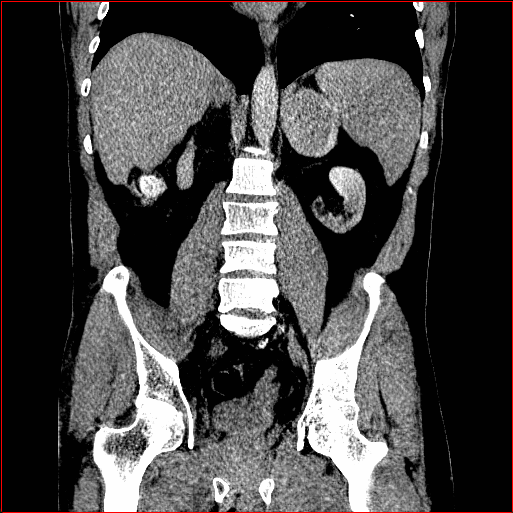

Figure 2: Qualitative comparison across axial (top row), sagittal (middle row), and coronal (bottom row) views. Columns correspond to different methods. MAISI-DDPM and MAISI-v2 in this figure are unconditional synthesis which do not use ControlNet or segmentation maps.

Qualitative Evaluation:

Figure 2 presents representative slices from the axial, sagittal, and coronal planes. GenerateCT (hamamci2024generatect) is a 2D model, so it lacks inter-slice consistency, leading to poor image quality in the sagittal and coronal views. MedSyn (xu2024medsyn) produces noticeably blurry results with mosaic-like artifacts, such as region inside the red box. HA-GAN (sun2022hierarchical) generates visually sharp images but with mosaic-like artifacts, such as region inside the red box. Also, its voxel spacing is not available, which limits its applicability in real-world medical imaging tasks. Moreover, all three methods are restricted to synthesizing small anatomical regions. In contrast, both MAISI and MAISI-v2 are capable of generating high-quality 3D volumes that span larger body regions while preserving fine anatomical details and realistic structure.